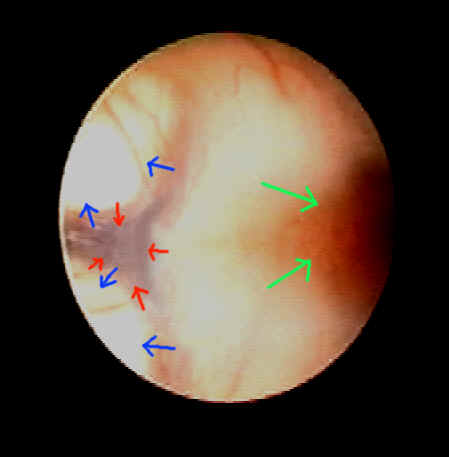

eine bestimmte Stelle am Boden des III. Ventrikels muß gefunden werden, die sehr dünn ist und wo das Loch angelegt werden kann. In diesem Fall ist es ein dreieckiger Bereich, der membranös dünn ist (rote Pfeile).

Diese Stelle liegt exakt zwischen zwei wichtigen Hirnstrukturen: Einerseits den Corpora mamilaria (blaue Pfeile), die bestimmte Funktionen für unsere Gedächtnisfunktion haben, und andererseits einem Bereich der Recessus pinealis heißt (grüne Pfeile). Hier nimmt die Hirnanhangdrüse (Hypophyse) ihren Ausgang und es werden dort bestimmte Signalstoffe des Körpers (Hormone) produziert, die sehr wesentliche Funktionen haben.

Das Bild zeigt bestens, dass die für die Perforation des Bodens des III. Ventrikel geeignete Stelle sehr klein ist und am besten mittels Endoskop also unter direkter Sicht aufgesucht wird.